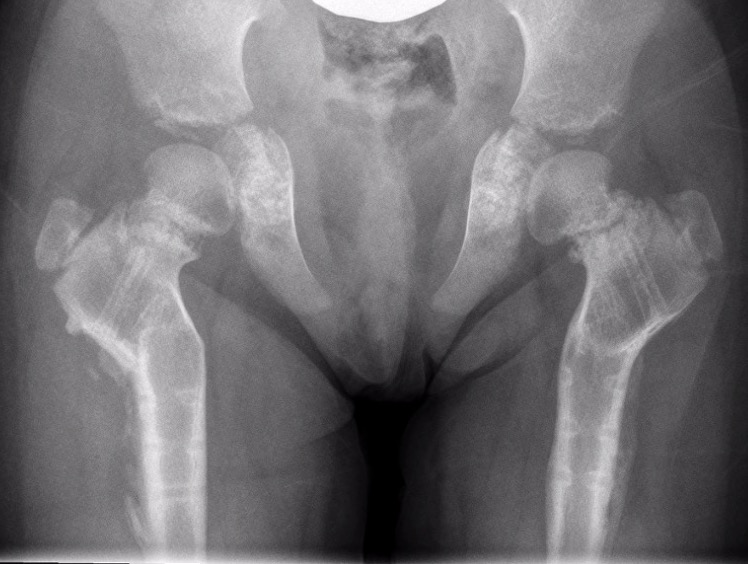

Dysplasia

- MED / SED www.boneschool.com/multiple-epithelial-dysplasia

- Achondroplasia www.boneschool.com/achondroplasia

- Fibrous Dysplasia www.boneschool.com/fibrous-dysplasia

Achondroplasia Multiple epithelia dysplasia